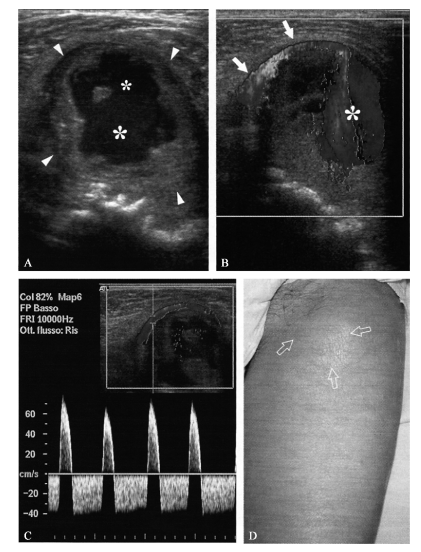

股动脉假性动脉瘤为血管壁撕裂后,血液从动脉漏入进入周围组织,常表现为动脉附近界限清楚的搏动性团块(图 一),常有附壁血栓,并部分充填于假性动脉瘤囊腔内。

一 股动脉假性动脉瘤,患者股总动脉穿刺后,腹股沟区出现一个搏动性隆起

腹股沟区12~5MHz超声灰阶图像(A)和彩色多普勒图像斜矢状断面(B)显示一个大的混合性肿物(箭头端)、壁厚中心腔形状不规整(* )。彩色多普勒超声显示肿物内存在涡流血流,通过一个细颈和移位的股动脉(箭头)相连。C. 在交通通道内的多普勒频谱显示为双向流速频谱,收缩期为前向血流,舒张期为反向血流。D. 照片显示股三角区软组织隆起(箭头),是为假性动脉瘤

假性动脉瘤内血流呈典型的红蓝交替的涡流(图一B)。

多普勒频谱分析示颈部的血流呈双向高速血流,收缩期由损伤的动脉进入瘤腔内,舒张期从瘤腔内排出,即所谓的往返信号(图一C)。